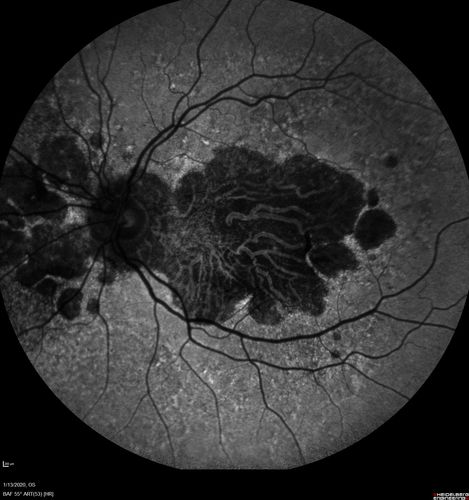

Severe Geographic Atrophy from Dry Age-Related Macular Degeneration

90 year old female with severe vision loss over the last few years.

VA 3/200 OD

1/200 OS

Geographic Atrophy from Age-related macular degeneration - Large areas